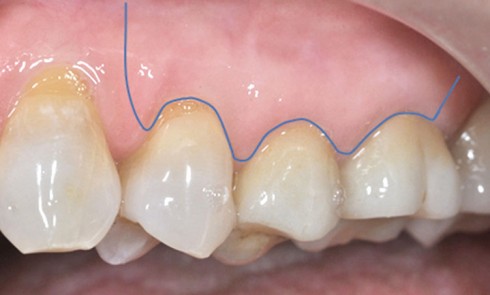

Article réservé à nos abonnés Que sait-on aujourd’hui des conséquences tissulaires du contact mini-vis/dent ?

Pour répondre à la question de la mise en place d’un implant au contact de tissus dentaires, voyons ce que...